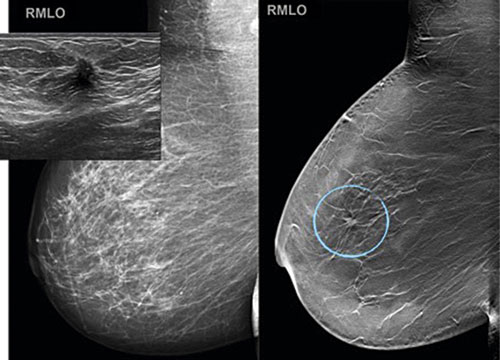

En förbättring av mammografitekniken utgör utvecklingen av tomosyntes, en skiktröntgenteknik liknande datortomografi, vilken ger ökad sensitivitet (Figur 1). Tomosyntes har visat sig vara användbar i såväl kliniskt sammanhang som screening [1]. I stora prospektiva screeningstudier (med mellan 7 000 och 25 000 kvinnor) har man funnit att tomosyntes som enskild modalitet eller i kombination med mammografi ger ca 30-procentig ökning av cancerdetektionen jämfört med konventionell screeningmammografi, och med bibehållen acceptabel nivå på återkallningsfrekvens (under 5 procent) [2-5].

Figur 1. En 11 mm stor lobulär cancer, histologisk grad 2, som inte är synlig med konventionell mammografibild (till vänster) men tydligt avbildad som en strålig förändring med tomosyntes (till höger, blå cirkel). Den infällda ultraljudsbilden visar ett utseende som är förenligt med malignitet: låg ekogenitet i lesionen med hyperekogen randzon samt ekoskugga [21]. Publiceras med tillstånd av Elsevier.